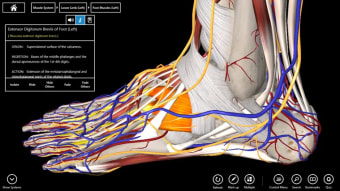

Essential Anatomy 3 bukanlah revolusi dalam rangkaian aplikasi Essential Anatomy tetapi menambahkan lebih banyak detail dan kemudahan penggunaan ke aplikasi. Hal yang paling mengesankan tentang Essential Anatomy 3 adalah tingkat detail dan model 3D yang dapat Anda manipulasi dan jelajahi. Essential Anatomy 3 tidak meninggalkan organ atau tendon terbuka - tingkat detailnya sama bagusnya dengan apa pun yang Anda temukan di Ensiklopedia medis.

Untuk mahasiswa kedokteran khususnya, Essential Anatomy adalah alat referensi yang luar biasa. Model 3D memungkinkan Anda untuk melihat dan memeriksa bagian tubuh manusia dari sudut mana pun memberikan detail luar biasa yang biasanya hanya dapat Anda alami melalui pembedahan.

Jika Anda perlu menemukan tulang, organ tertentu atau otot, Anda cukup menelusuri berdasarkan bagian tubuh dan Essential Anatomy akan menyorot dengan tepat di mana mereka berada dengan deskripsi bermanfaat dari setiap bagian. Satu-satunya hal yang kurang adalah animasi organ dan otot yang sedang beraksi.